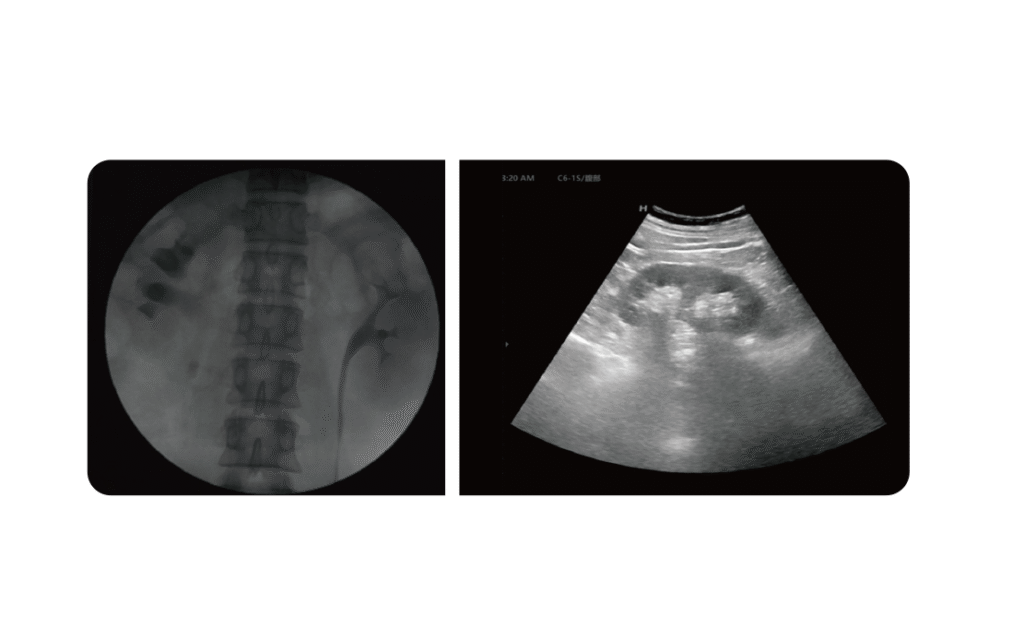

Dual Imaging Modes

- Dual imaging modes using X-ray and ultrasound

- Outline ultrasound allows shorter skin to stone distance and continuous real-time monitoring